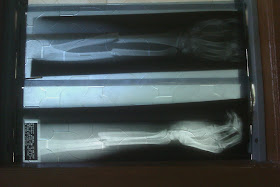

Yang ni filem x-ray dia... kami letak kat tingkap sbb nk tangkap gambonye :P